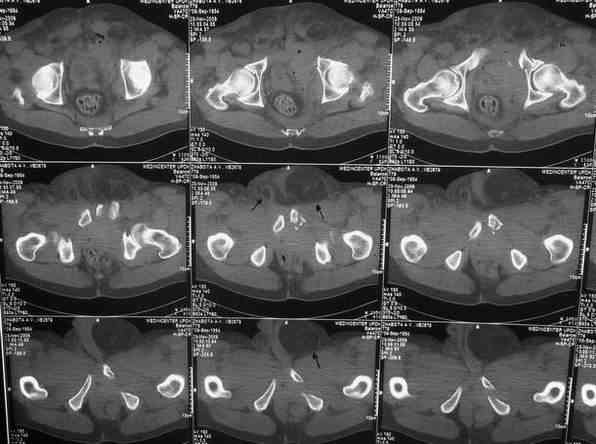

У больного оскольчатые переломы левых лонной и седалищной костей со

смещением отломков, разрывом симфиза и распространением линии перелома

на вертлужную впадину; переломы крыла левой подвздошной кости и правой

боковой массы крестца без смещения; разрыв уретры. За последние годы

настоящее время имеются 2 паховомошоночные грыжи, левая - значительных

размеров (на одной из КТ-грамм указаны стрелками). Мошонка огромная,

но не напряженная.